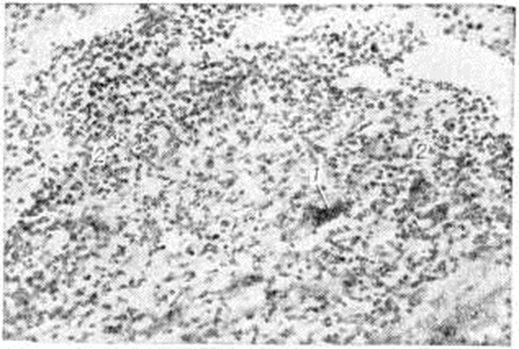

Дистрофический компонент воспаления, под которым имеется в виду морфологический отражение нарушений обмена в миокарде (а не сами эти нарушения, то есть миокардиодистрофия в понимании Г. Ф. Ланга), объединяет все формы дистрофических, некробиотических и некротических процессов, которые развиваются в миокарде при различных обстоятельствах, не имеющие какой-либо специфики при включении их в воспалительный комплекс: белковую (паренхиматозную), липидную, водяночно-вакуольную дистрофию (смотри полный свод знаний Дистрофия клеток и тканей). Гистохимические и электронно-микроскопические исследования не выявляют каких-либо особенностей дистрофического компонента воспаления, отличных от известных форм и стадий дистрофии миокарда различного происхождения. Распространённый очаговый кардиомиоцитолиз приводит к опустошению более или менее обширных участков миокарда (рисунок 3), их депаренхиматизации, при которой в этих участках от сократительного миокарда остаётся только аргентофильная строма с сохранившимися в ней остатками кардиомиоцитов и мелкими глыбками бурого пигмента. Эти процессы могут сопровождаться лишь незначительной клеточной реакцией в строме миокарда. В дальнейшем происходит сближение мышечных волокон по периферии депаренхиматизированных гнёзд с последующим замещением их грануляционной и зрелой рубцовой тканью, то есть наблюдается исход в кардиосклероз. Выраженный некробиоз, переходящий в некроз, характеризуется мелко и крупно-глыбчатым распадом цитоплазмы кардиомиоцитов; при этом возможно длительное сохранение сарколеммы и ядер. Интенсивность дистрофических процессов варьирует в широких пределах в зависимости от интенсивности патогенного воздействия, его преимущественной паренхимотропности. Некробиотические процессы приводят к развитию обширных участков некроза миокарда с превращением этих участков в мелкозернистый эозинофильный детрит, окаймлённый зоной лимфогистиоцитарного инфильтрата. Подобные морфологические изменения могут напоминать феномен Артюса (смотри полный свод знаний Артюса феномен) .